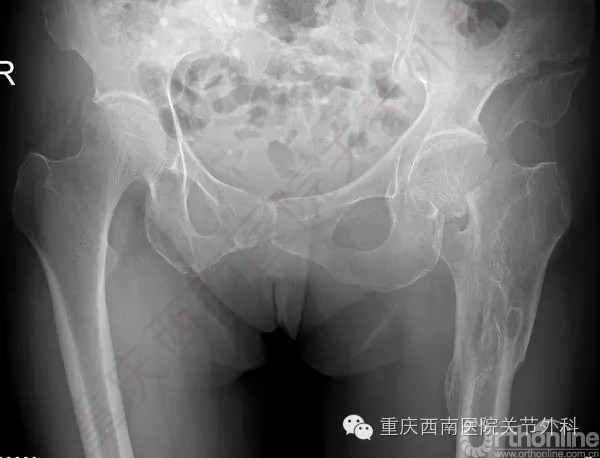

2016年5月17日,来自遵义市的赵女士切身体验到了这一快速高效精准医学技术所带来的好处。赵女士64岁,7天前不幸摔倒导致左侧股骨颈骨折(图1)

颈骨折是老年女性常见骨折,但是她辗转于贵州几家医院均未得到确切的治疗方案。原因是(图2)

1996年的车祸导致她左侧股骨骨折形成严重的畸形愈合,股骨前后错开,髓腔封闭,类似“双截棍”,脊柱固定侧弯(图3)。